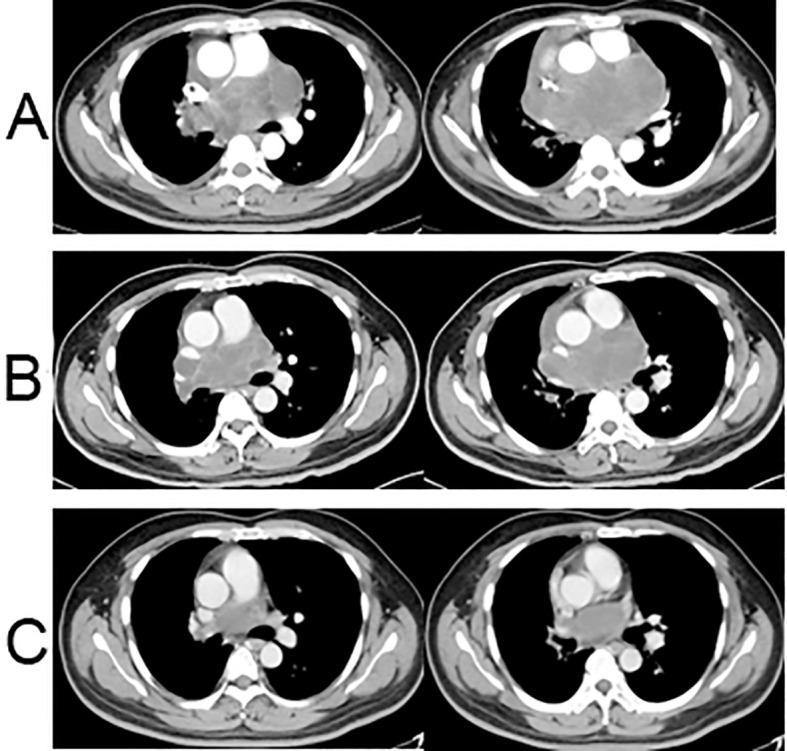

Pulmonary arterial intimal sarcoma (PAIS) is a rare malignant mesenchymal tumor often associated with an unfavorable prognosis and lacks a standardized treatment approach to date. This report presents a notable case of PAIS treated with neoadjuvant therapy involving anlotinib concomitantly administered with chemotherapy of ifosfamide and pirarubicin, which resulted in a favorable outcome. A 38-year-old man was admitted to our hospital with chest tightness, cough, and dyspnea, all of which had persisted for more than a week. Initial evaluation via chest computed tomography (CT) revealed a sizable posterior mediastinal tumor measuring 11.9 × 7.6 cm. A CT-guided biopsy was performed, and pathological findings confirmed the diagnosis of PAIS. Efficacy evaluation showed slow progress after one cycle of chemotherapy with ifosfamide and pirarubicin. To enhance treatment outcomes, we incorporated anlotinib as a neoadjuvant therapy alongside ifosfamide and pirarubicin. Subsequent CT imaging demonstrated a significant reduction in tumor size, and the patient experienced notable alleviation of symptoms. The patient then underwent surgery, radiation, and subsequently, maintenance treatment with anlotinib for one year. No severe drug-related side effects were observed. The patient achieved progression-free survival of 25 months following administration of anlotinib. Thus, the combination of anlotinib with ifosfamide and pirarubicin demonstrated significant efficacy and safety. This approach holds promise as an effective therapeutic strategy for managing unresectable, locally advanced, or advanced PAIS. However, further clinical studies are necessary to validate these findings.

肺动脉内膜肉瘤(PAIS)是一种罕见的恶性间叶组织肿瘤,通常预后不良,且迄今为止缺乏标准化的治疗方法。本报告介绍了一例值得注意的PAIS病例,该病例采用了新辅助治疗,将安罗替尼与异环磷酰胺和吡柔比星化疗联合使用,取得了良好的治疗效果。一名38岁男性因胸闷、咳嗽和呼吸困难入院,这些症状持续了一周多。胸部计算机断层扫描(CT)初步评估显示,后纵隔有一个较大的肿瘤,大小为11.9×7.6厘米。进行了CT引导下活检,病理结果确诊为PAIS。疗效评估显示,使用异环磷酰胺和吡柔比星进行一个周期化疗后病情进展缓慢。为提高治疗效果,我们将安罗替尼作为新辅助治疗药物与异环磷酰胺和吡柔比星联合使用。随后的CT成像显示肿瘤大小显著缩小,患者症状明显缓解。患者随后接受了手术、放疗,随后使用安罗替尼进行了一年的维持治疗。未观察到严重的药物相关副作用。使用安罗替尼后,患者实现了25个月的无进展生存期。因此,安罗替尼与异环磷酰胺和吡柔比星联合使用显示出显著的疗效和安全性。这种方法有望成为治疗不可切除、局部晚期或晚期PAIS的有效治疗策略。然而,需要进一步的临床研究来验证这些发现。